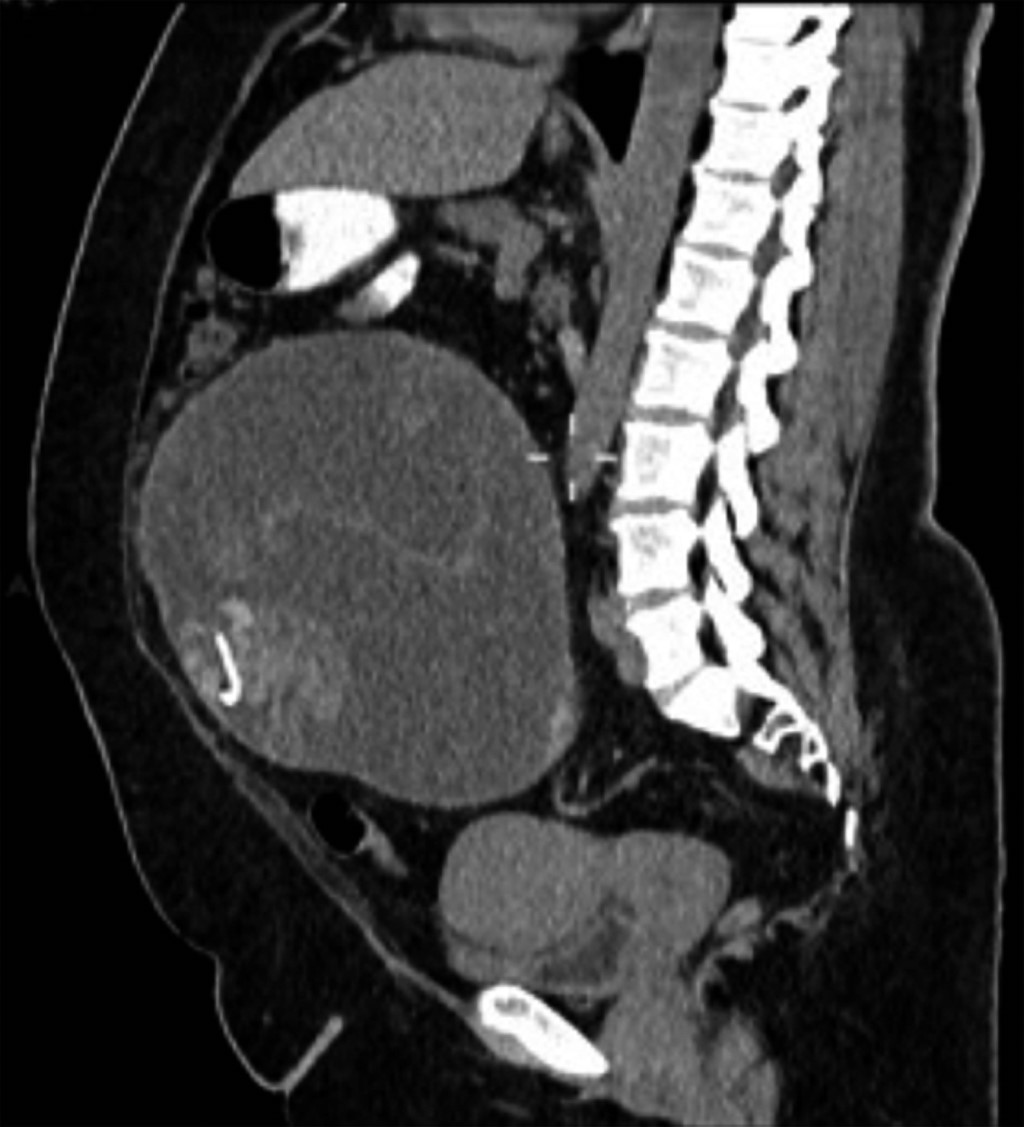

Intraabdominal textiloma: frequent entity but not documented of retained surgical material

It is estimated that retained surgical materials occur in 1:5,500 surgeries, with 50% diagnosed when the patient is discharged. Gauze pads are the most common cause of surgical retention (48-69%), and counting them is essential to prevent this problem. Although only 77% of counts are performed correctly, preventive protocols such as using surgical material impregnated with a radiopaque tracer and X-rays can minimize the damage. It is important to report and document these cases to improve the quality of medical care and reduce the risk of errors in future surgeries.

Figure 1

Figure 2

Figure 3